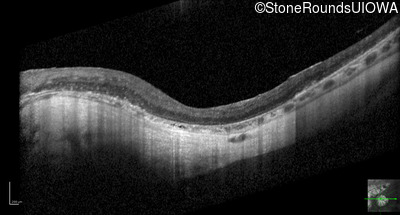

Optical Coherence Tomography - Left - 20/100

Exemplar / OCT Stack

OCT Stack